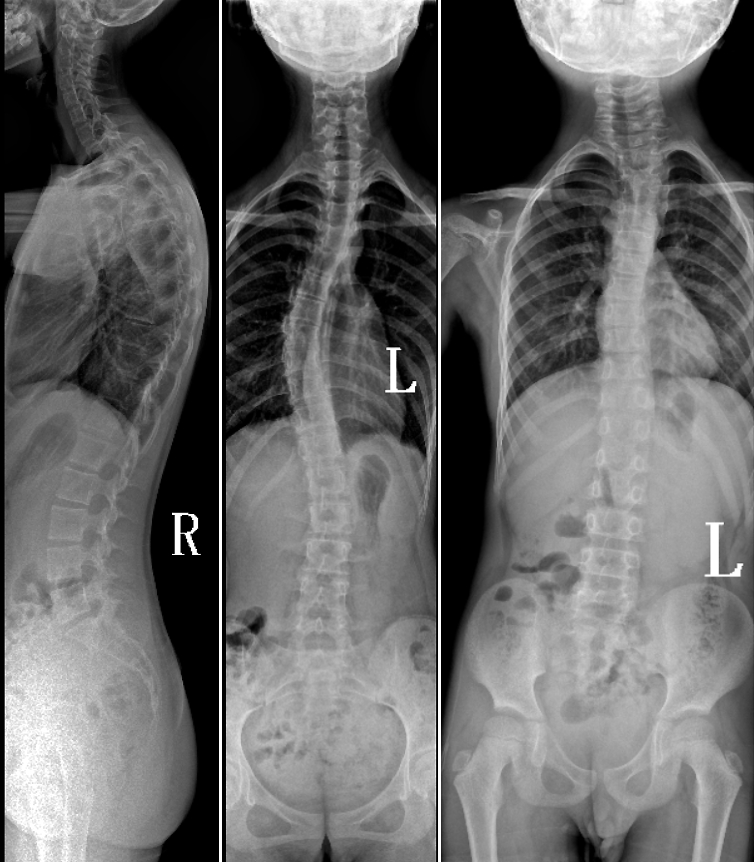

DR是临床骨科的重要检查手段之一。在骨科检查中,脊柱矫形、长骨骨折、腰椎退行性病变等,需要采集脊柱、下肢全景图像,辅助医生临床诊断,从而制定科学的治疗方案,糖心vlog 的大视野平板动态DR就像是一座桥梁,连接起现代医疗技术与当地人民的医疗需求。

糖心vlog 自主研发的大视野平板动态,采用17"*34"的有效视野,一次曝光即可得到全脊柱或全下肢影像。相较于多张摄影再软件拼接的DR设备,PLX8600解决了拼接图像存在密度不均匀,拼接处图像配准和放大效应等问题,给临床带来了真正的大视野影像解决方案。

除了常规静态摄影外,PLX8600的大平板具备动态透视和点片功能,能够很好地观察复杂部位病灶,有效地抓取关键帧,降低患者多次摄片的概率。如:全脊柱状态评估、长骨关节活动度、下肢静脉造影瓣膜功能评估、消化道功能评估、脊髓造影等更多大视野临床应用,“多面手”都能轻松应对。